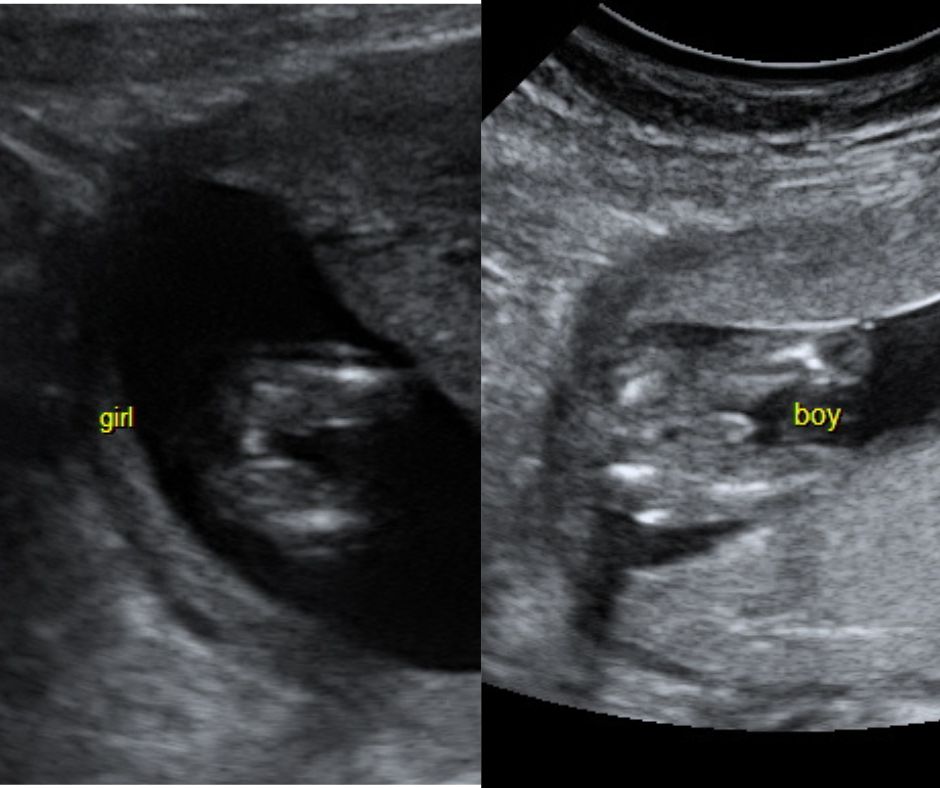

Gender Scans

One of the great thrills of ultrasound is that at the right time we can show and tell you the sex of your baby.

Gender scans can be done with nearly 100% accuracy from about 16 weeks of gestation.